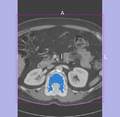

• An unique feature in the planning part were tumor segmentation and ablation volume planning, taking ablation magin into account.